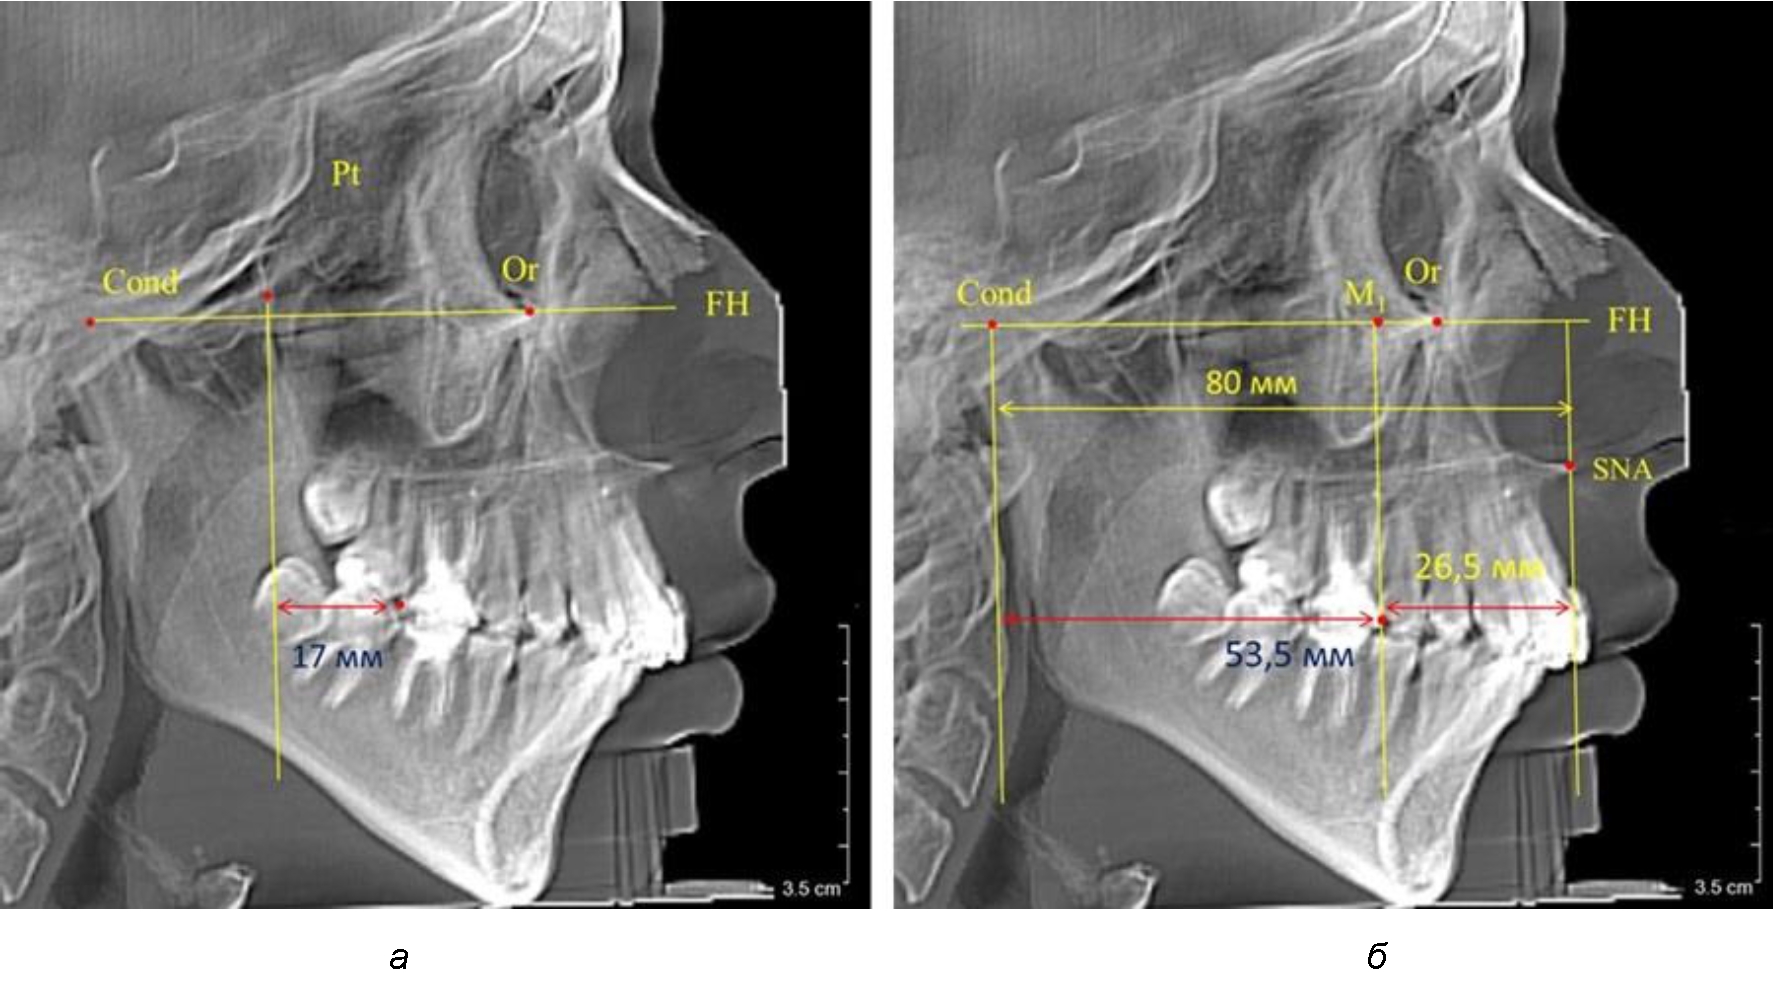

После прорезывания вторых постоянных моляров кондилярно-спинальный увеличивался до 80 мм.

Дистальная поверхность первого постоянного моляра отстояла от крыловидной вертикали на величину, составляющую около 18 мм, что, так же, как и в предыдущих периодах прикуса, было близким по значению к данным R. E. McDonald, а именно возраст, плюс 3 мм.

Обращает на себя внимание отношение глубины гнатического отдела лица к дистальному отделу, а именно к кондилярно-молярному расстоянию, которое, вне зависимости от сагиттальных размеров, составляло 1 : 1,5.

Рентгенограмма 16-летнего ребенка, с реперными линиями и анализируемыми линейными параметрами по двум используемым методам, представлена на рис. 6.

Рис. 6. Особенности положения первых моляров по R. E. McDonald (а) и по предложенному методу (б) у ребенка 16 лет